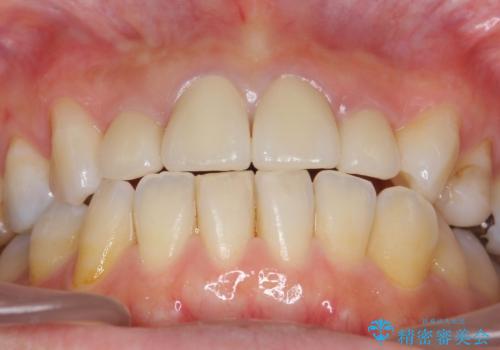

黒ずんだ見栄えの悪い前歯をきれいにしたい

- 「黒ずんで、見栄えの悪い前歯をきれいにしたい。」と、前歯のセラミック治療を希望され来院されました。

全て根管治療のすでになされている歯の変色で、オールセラミッククラウンによる審美性の改善を計画します。

自然で美しい前歯の仕上がりとなり、大変満足していただくことができました。